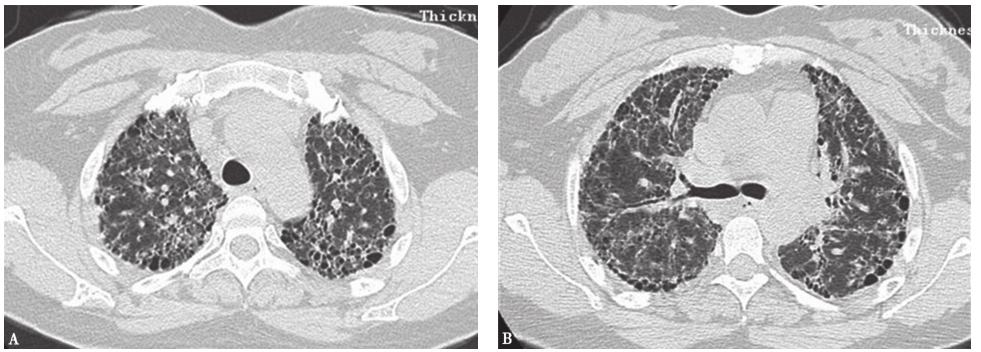

巨细胞间质性肺炎(giant cell interstitial pneumonia,GIP):是暴露于含有钴、碳化钨等硬金属及其化合物引起的少见职业相关性间质性肺疾病。其典型胸部CT表现为弥漫性磨玻璃影、小结节影、广泛网状影和牵拉性支气管扩张改变,以及大小不等的实变影(图12)。晚期患者可见肺部广泛的结构扭曲和蜂窝样改变。GIP最终诊断应该根据职业接触史、影像学特征和病理学等证据。本例患者从事钻孔工作8年,接触金属粉尘较多,有职业接触史,影像学特征也较符合GIP,但仍需获得病理学检查结果以明确诊断。

图12巨细胞间质性肺炎胸部影像学表现

男性患者,32岁,从事刀具磨制工作9年,经支气管肺活检病理证实为巨细胞间质性肺炎。CT示两肺散在磨玻璃影、小结节影、小片实变影、牵拉性支气管扩张